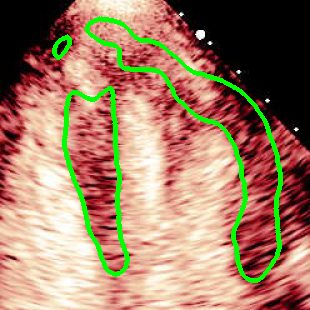

For variations caused by low quality images such as those of low resolution or significant artifacts, however, the unique ground truth may not be available. Take the myocardial segmentation task of Myocardial Contrast Echocardiography (MCE) as an example. An inter-observer experiment was conducted among five experienced cardiologists, and Fig. 1(a)(b) visualize the annotations of two images from three of these cardiologists. It can be seen that the labels by different cardiologists vary significantly, especially in locations where the intensity information of myocardium is very similar to the background. Table 1 shows the average Dice of the annotation of each cardiologist, using one of the others’ as the ground truth, over 180 images. We can observe that none of the Dice is above 0.9, some even under 0.8, confirming significant variations among the annotations. In this case, as the variations are caused by the image quality, even these cardiologists cannot tell which annotation is better than others, and a majority vote for ground truth would not make sense sometimes as can be seen in Fig. 1(c)(d). For this reason, we cannot obtain a unique ground truth in the evaluation process and the traditional metrics such as Dice and IoU cannot be used.